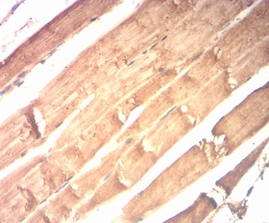

CKM Mouse Monoclonal antibody[1D10F]

IHC    1/200 - 1/1000